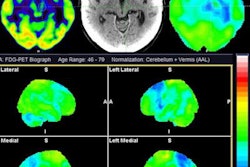

According to the findings, a pattern of lower cortical, subcortical and limbic 5-HTT availability and higher cortical beta-amyloid deposits on the PET scans distinguished the MCI participants from the healthy older controls, a statistically significant correlation (p < 0.00001).

PET scans of 5-HTT and beta amyloid in healthy controls and individuals with MCI. Mean distribution volume ratio images of healthy controls (left panels) and MCI (right panels) and an MRI template (bottom panel). Image courtesy of NeuroImage: Clinical through CC BY 4.0.In addition, the spatial covariance pattern of the two markers corresponded with neuropsychiatric symptoms in the MCI group, the researchers reported.